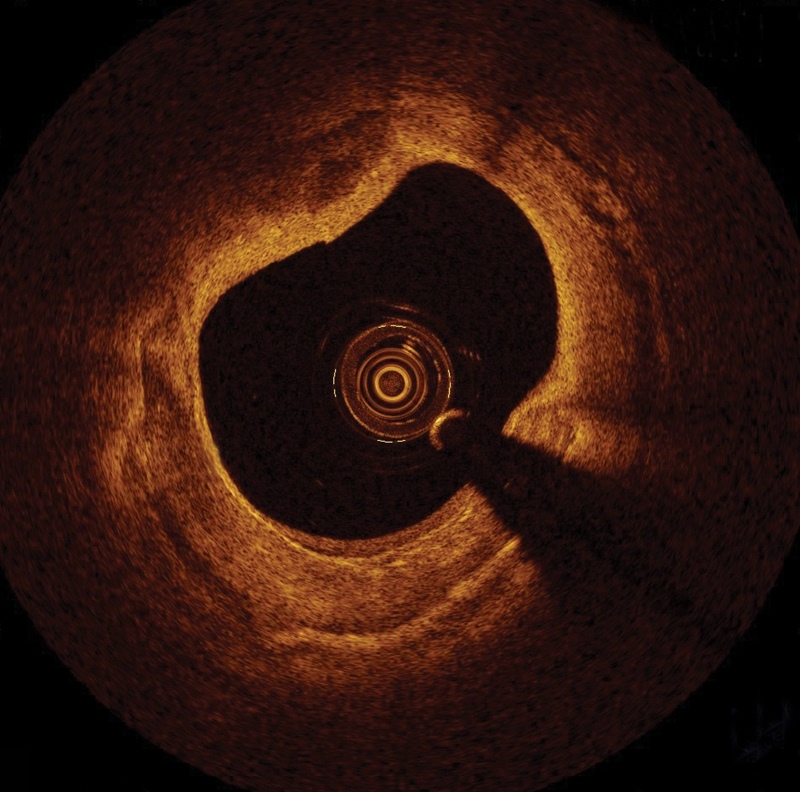

OCT images allow physicians to view the inside of a blood vessel. Credit: St Jude Medical.